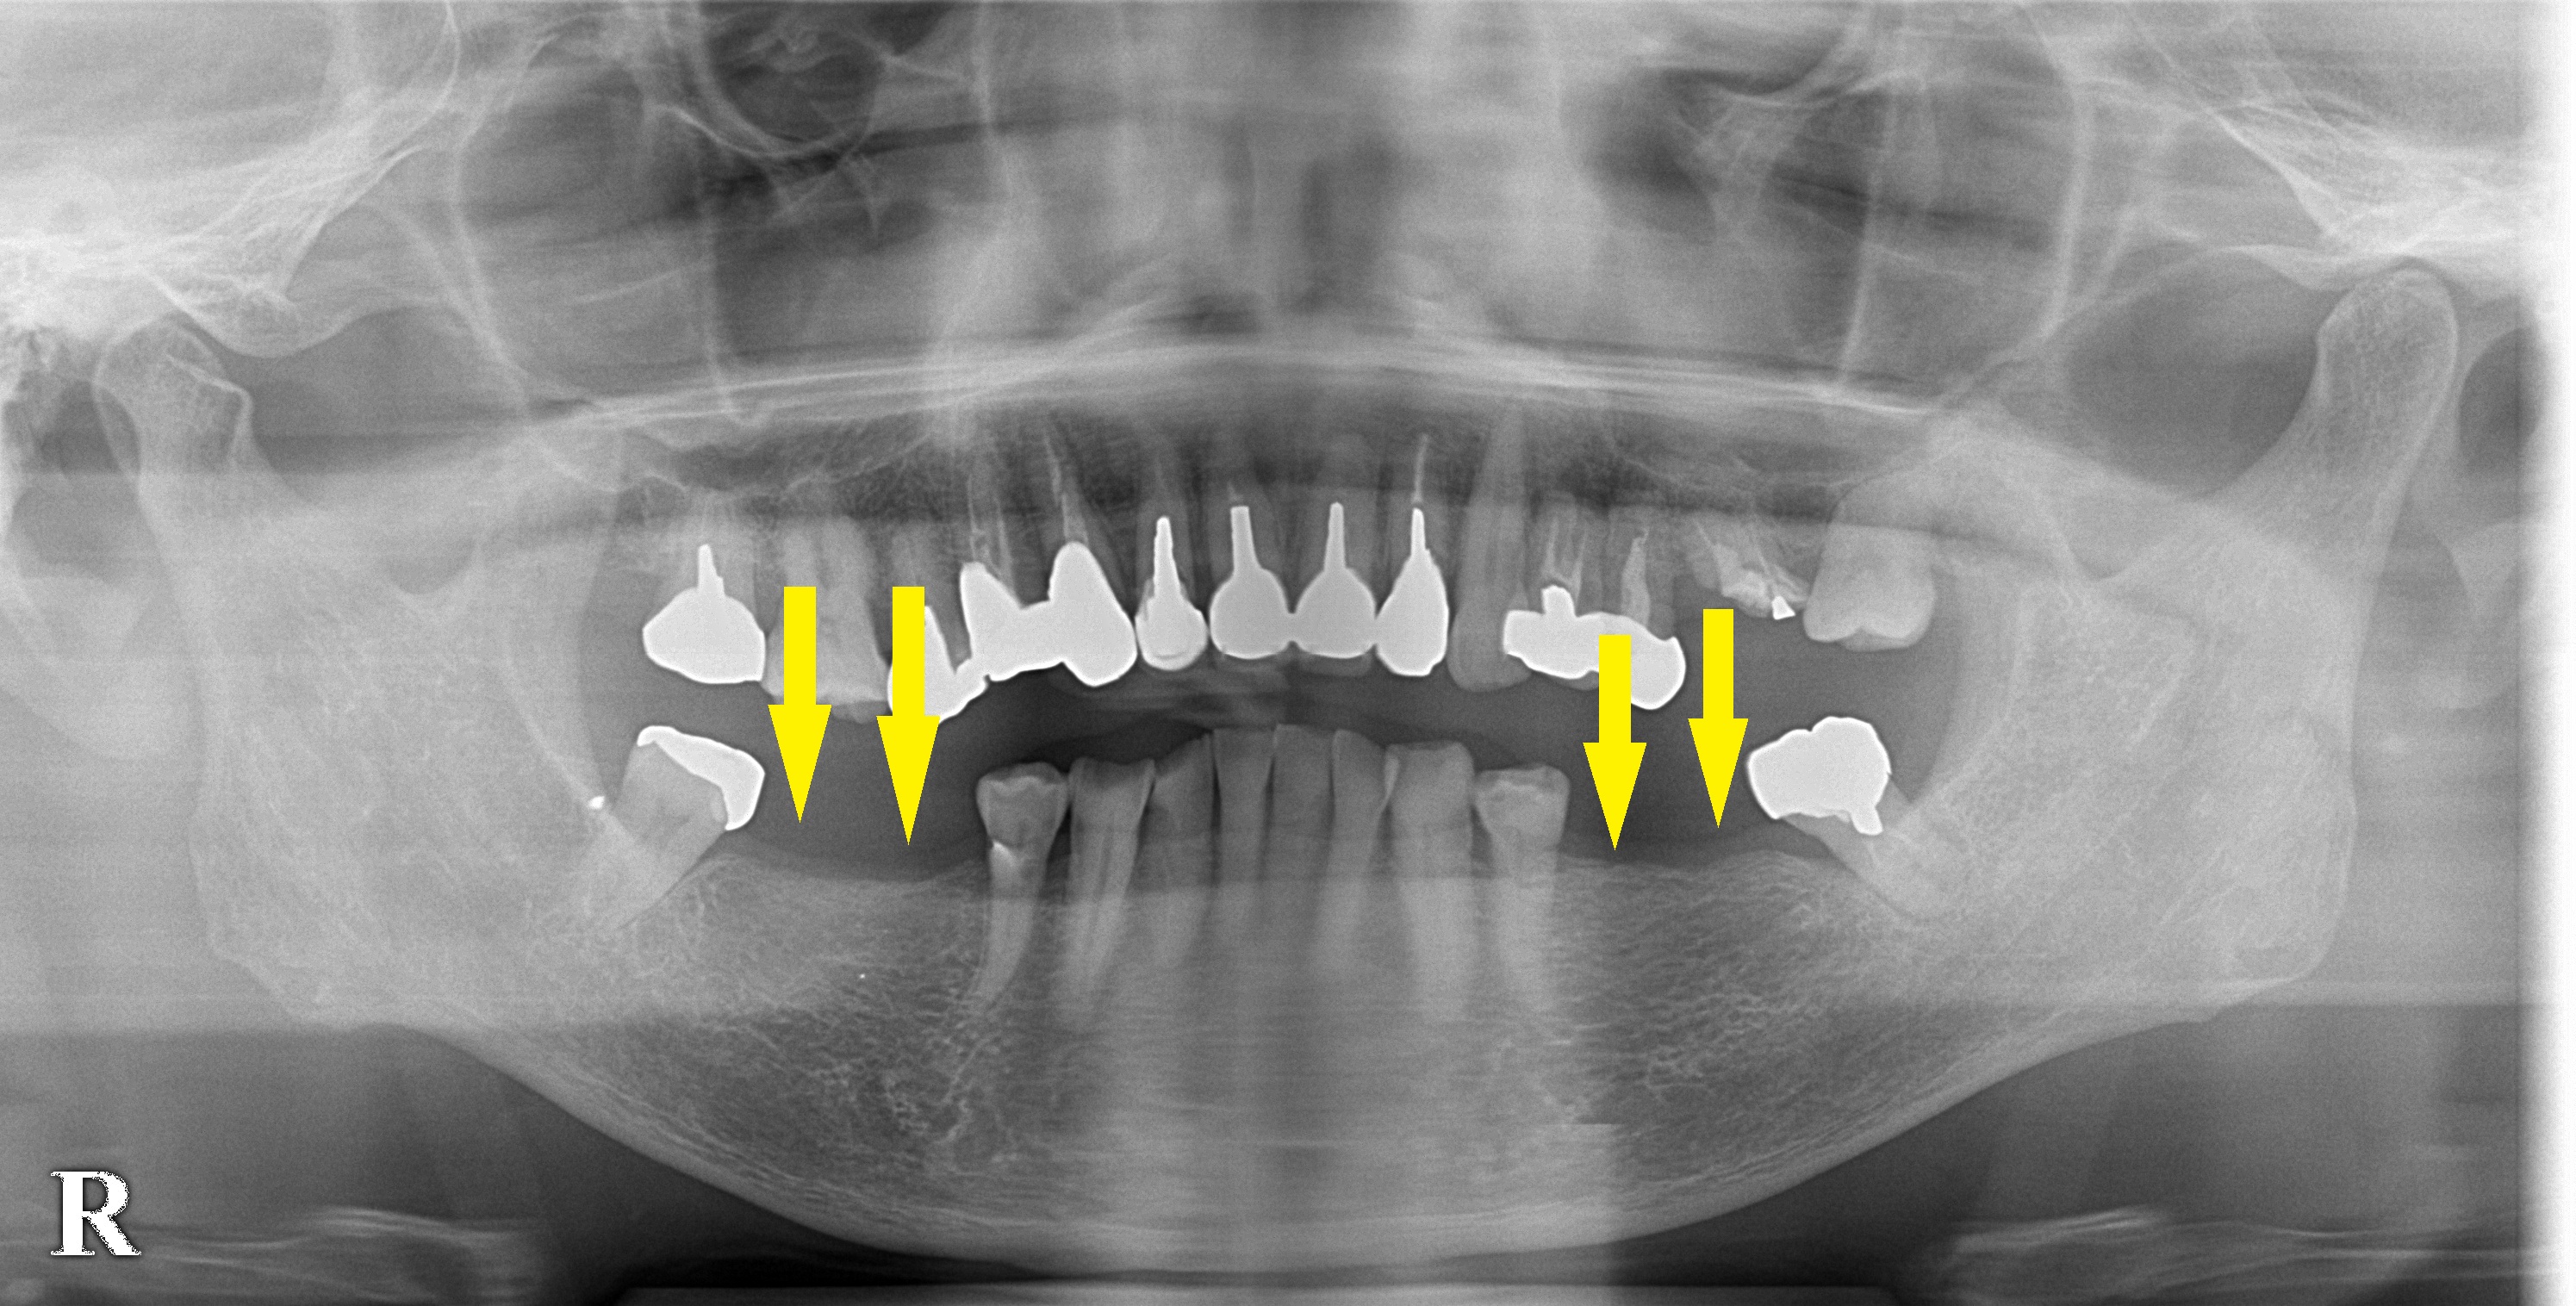

両側の臼歯を同時にインプラントへ 今週のインプラント症例 2020.08.272026.01.19 患者様は名古屋在住の50代女性。 数年前に両側の臼歯を抜歯、その後、義歯を使用されていたとのことですが決して快適ではなかったそうです。 ご友人にインプラント治療を勧められ、当院に相談にお出でになりました。 レントゲン写真、CTにて骨量は問題なかったのですが、歯が抜けて、長い期間が経過しているため、固い歯肉の幅が狭くなってしまっていました。 本日はインプラントの埋入術のみを行ないましたが、手術部位が治癒したら固い歯肉の幅を拡げる手術を行う予定です。 症例・コラム一覧に戻る